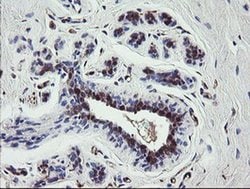

TSC22D1 Monoclonal Antibody (OTI1A5), Invitrogen™

TSC22 domain family protein, or TSC22, is a transcription factor that belongs to the large family of early response genes. This transcriptional repressor is known to act on the C-type natriuretic peptide (CNP) promoter. TSC22 belongs to the TSC-22/Dip/Bun family and is an intracellular protein that may be found in the cytoplasm or nucleus. This transcription factor is known to regulate cell growth, differentiation and cell death and is involved in modulating the transcriptional activity of Smad3 and Smad4. This protein is ubiquitously expressed in most tissues and widely in both fetal and adult tissues. It is generally expressed in aortic endothelial cells, and induced by cytokines, including TGFB. These proteins may be possible therapeutic targets of leukemia and prostate cancer.

| Immunohistochemistry (Paraffin), Western Blot | |